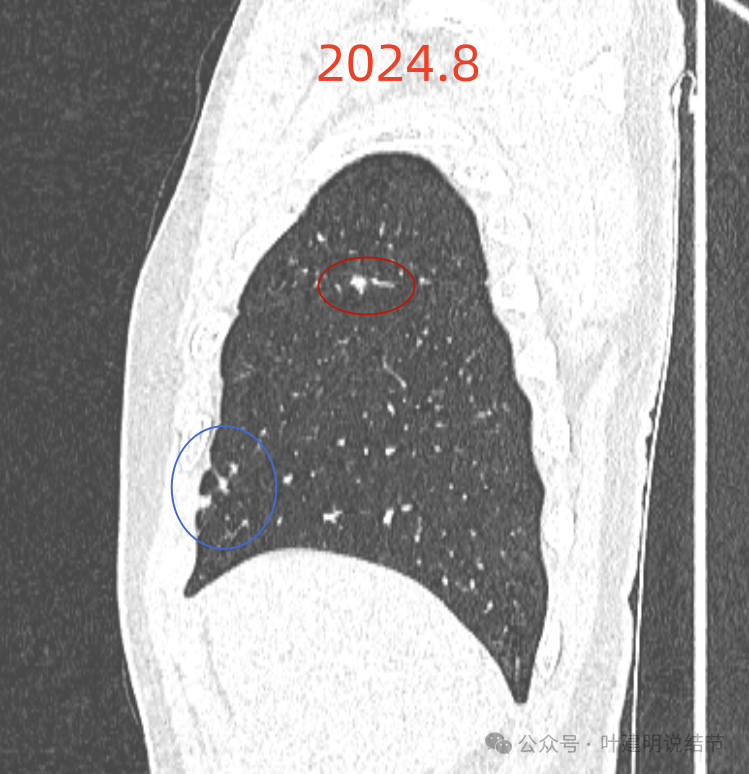

我们先来看2024年8月时的影像:

右上叶实性结节,边缘不光滑,有血管征,内部密度稍不均,整体轮廓较为清楚。

主病灶冠状位见血管紧挨,膨胀性不够。

主病灶矢状位见病灶略显模糊,边缘相对较为平直。